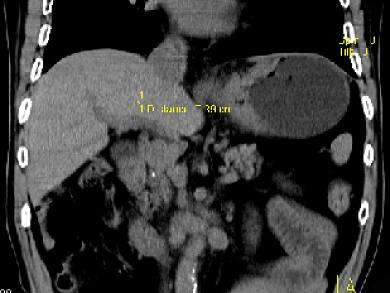

问题 男,75岁,吞咽有梗阻感,消瘦、乏力、中上腹痛,影像检查如图,最可能的诊断是 ( )

选项 A.食管癌 B.胃窦癌 C.贲门癌 D.慢性胃炎 E.胃淋巴瘤

答案 C